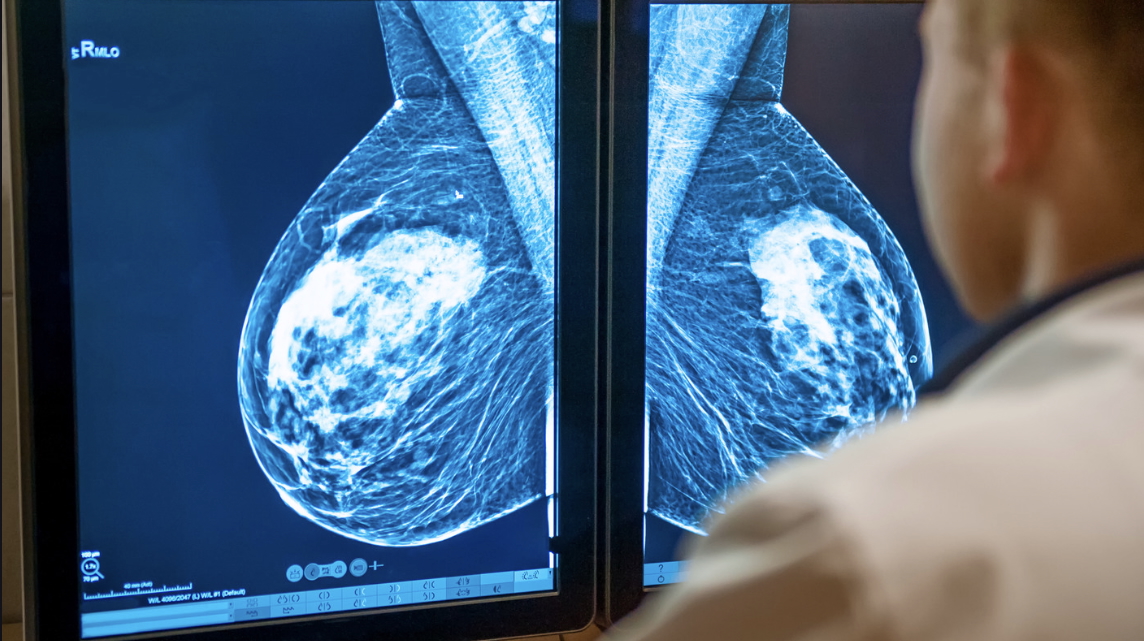

Both dense tissue and early-stage cancers appear as white on a mammogram.

Not only does having dense breasts make it harder to spot cancer in a mammogram, Peter Mac-led research has found dense breasts promote more aggressive cancer growth and could be a factor when personalising treatment.

The research, led by Associate Professor Kara Britt and Dr Dane Cheasley, has identified important biological differences in the tumour microenvironment when comparing breast cancers from high versus low density breasts.